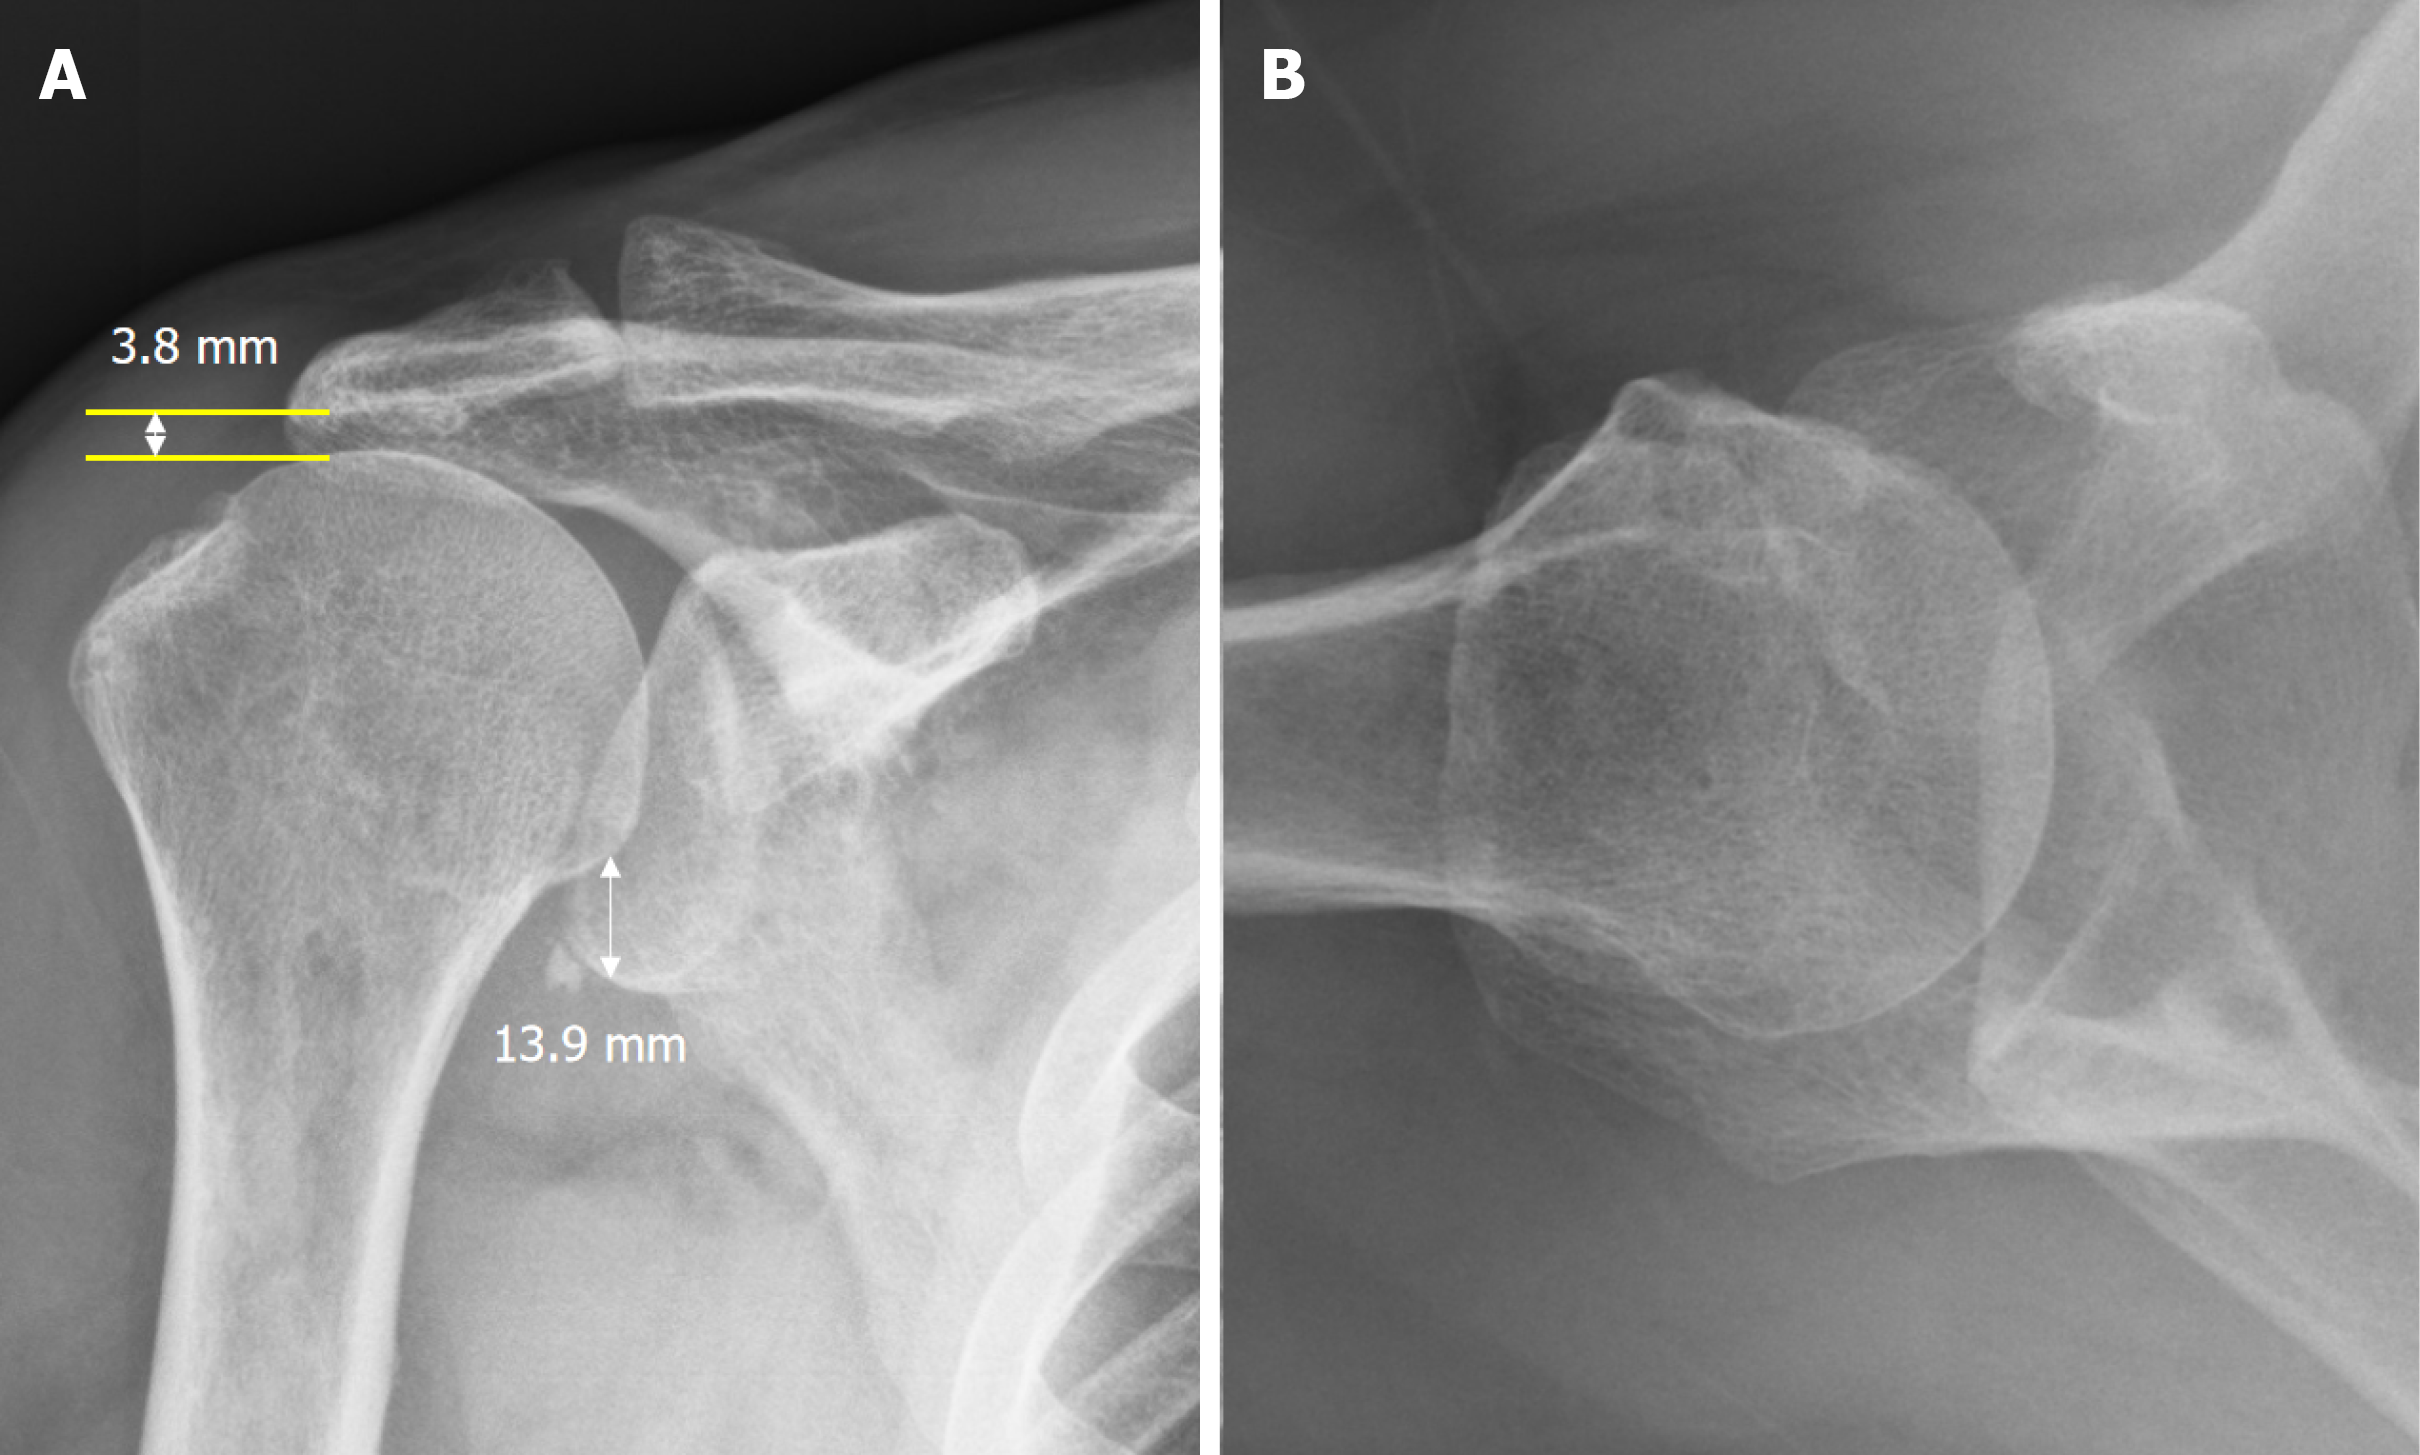

Figure 2 Shoulder radiograph after reduction.

Radiography confirmed successful reduction of the dislocated shoulder. However, the acromiohumeral interval was 3.8 mm, and the inferior glenohumeral distance was 13.9 mm (Hamada-Fukuda grade 2), suggesting a massive rotator cuff tear. A: Shoulder anteroposterior radiograph; B: Shoulder axillary radiograph.